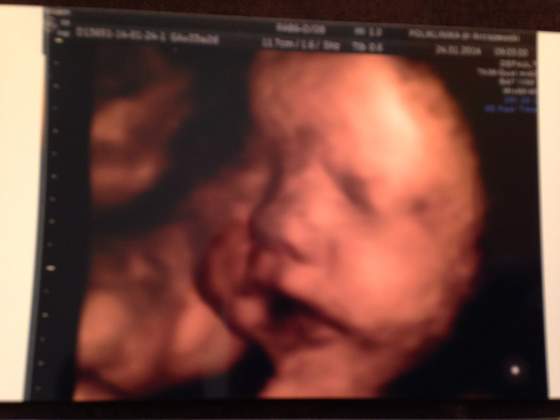

w ciąży z Martyną nie miałam tego usg 3d, jakoś tak w sumie nie wiem czemu, nawet o tym nie pomyślałam. teraz właśnie myślę, ale skoro na zwykłym usg kiepsko widać to czy na usg 3/4d będzie lepiej? no i jednak to sporo kasy dlatego ginka mnie nie namawia. powiedziała, że może być nie za dobrze widać, dlatego mam dylemat :-( i chyba się jednak nie zdecyduję. niech mi tylko płeć potwierdzi, bo jeszcze nie wiadomo na 100% ;-)